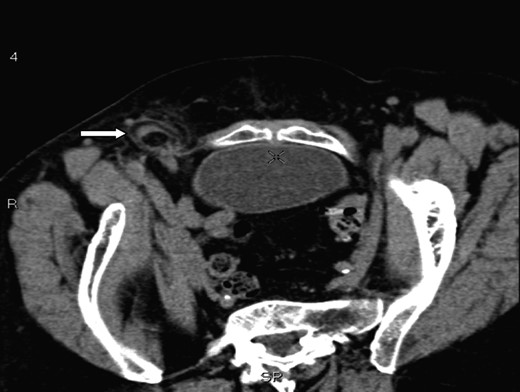

A 70-year-old female was referred by her general practitioner to our radiology department after presenting with a painless right groin swelling. An ultrasound scan showed a lymph node in the right groin with surrounding fluid and unusual appearances not typical of a hernia. A limited CT scan was subsequently performed which revealed a right femoral hernia containing the tip of the vermiform appendix with surrounding inflammatory change and an associated enlarged lymph node in keeping with a De Garengeot's hernia (Figs 1–3). On questioning, the patient first noticed the lump 2 weeks prior to presentation and said that it has gradually increased in size. It was not painful and she had no obstructive symptoms. Her medical history included COPD, breast cancer and a past history of tuberculosis.

A axial section illustrating a right femoral hernia through the femoral canal at the level of pubic tubercle.